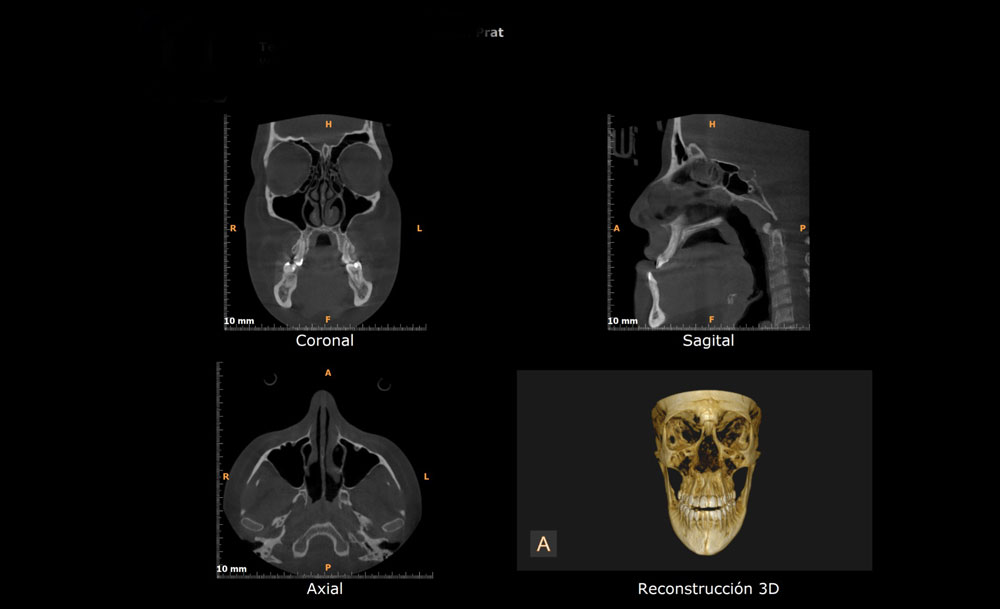

La TC Cone Beam es una tecnología que permite el escaneado y la adquisición de volumen especifico de la cabeza del paciente y que genera datos en 3D, con utilización de dosis de radiación mucho menor que la dosis utilizada por los escaner médicos.

La TC Cone Beam presenta numerosas ventajas sobre las otras modalidades de exámenes debido a su exactitud, a su alta velocidad de adquisición y a su seguridad.

- Se pueden visualizar imágenes de alta calidad en los tres planos del espacio.

- Reconstrucciones tridimensionales a escala real de 1:1.